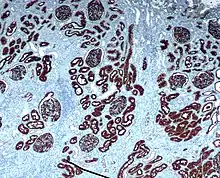

Immunohistochemistry (IHC) is the most common application of immunostaining. It involves the process of selectively identifying antigens (proteins) in cells of a tissue section by exploiting the principle of antibodies binding specifically to antigens in biological tissues.[1] IHC takes its name from the roots "immuno", in reference to antibodies used in the procedure, and "histo", meaning tissue (compare to immunocytochemistry). Albert Coons conceptualized and first implemented the procedure in 1941.[2]

- Chromogenic immunohistochemistry (CIH), wherein an antibody is conjugated to an enzyme, such as peroxidase (the combination being termed immunoperoxidase), that can catalyse a colour-producing reaction.[3]

Immunohistochemical staining is widely used in the diagnosis of abnormal cells such as those found in cancerous tumors. Specific molecular markers are characteristic of particular cellular events such as proliferation or cell death (apoptosis).[4] Immunohistochemistry is also widely used in basic research to understand the distribution and localization of biomarkers and differentially expressed proteins in different parts of a biological tissue.